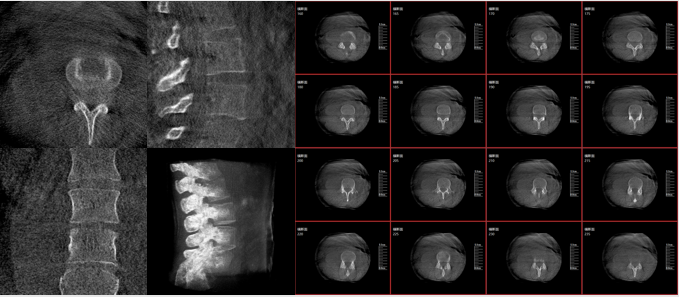

从图中可以看到二维影像能够提供目标区域在某一个平面的重叠影像,虽然因为人体不同组织的密度差异,使得图像具有较为丰富的信息量,但组织间的相互重叠还是会出现,诸如空间位置等众多信息在影像中遗失或不可辨认的情况,影响了医生对信息的收集与应用。

术中三维影像

而三维影像的MPR图像组可以通过不同平面的切分,使成像区内更丰富的信息得以呈现。尤其是二维影像无法涉及的横断面,提供了另一个空间维度的信息量。